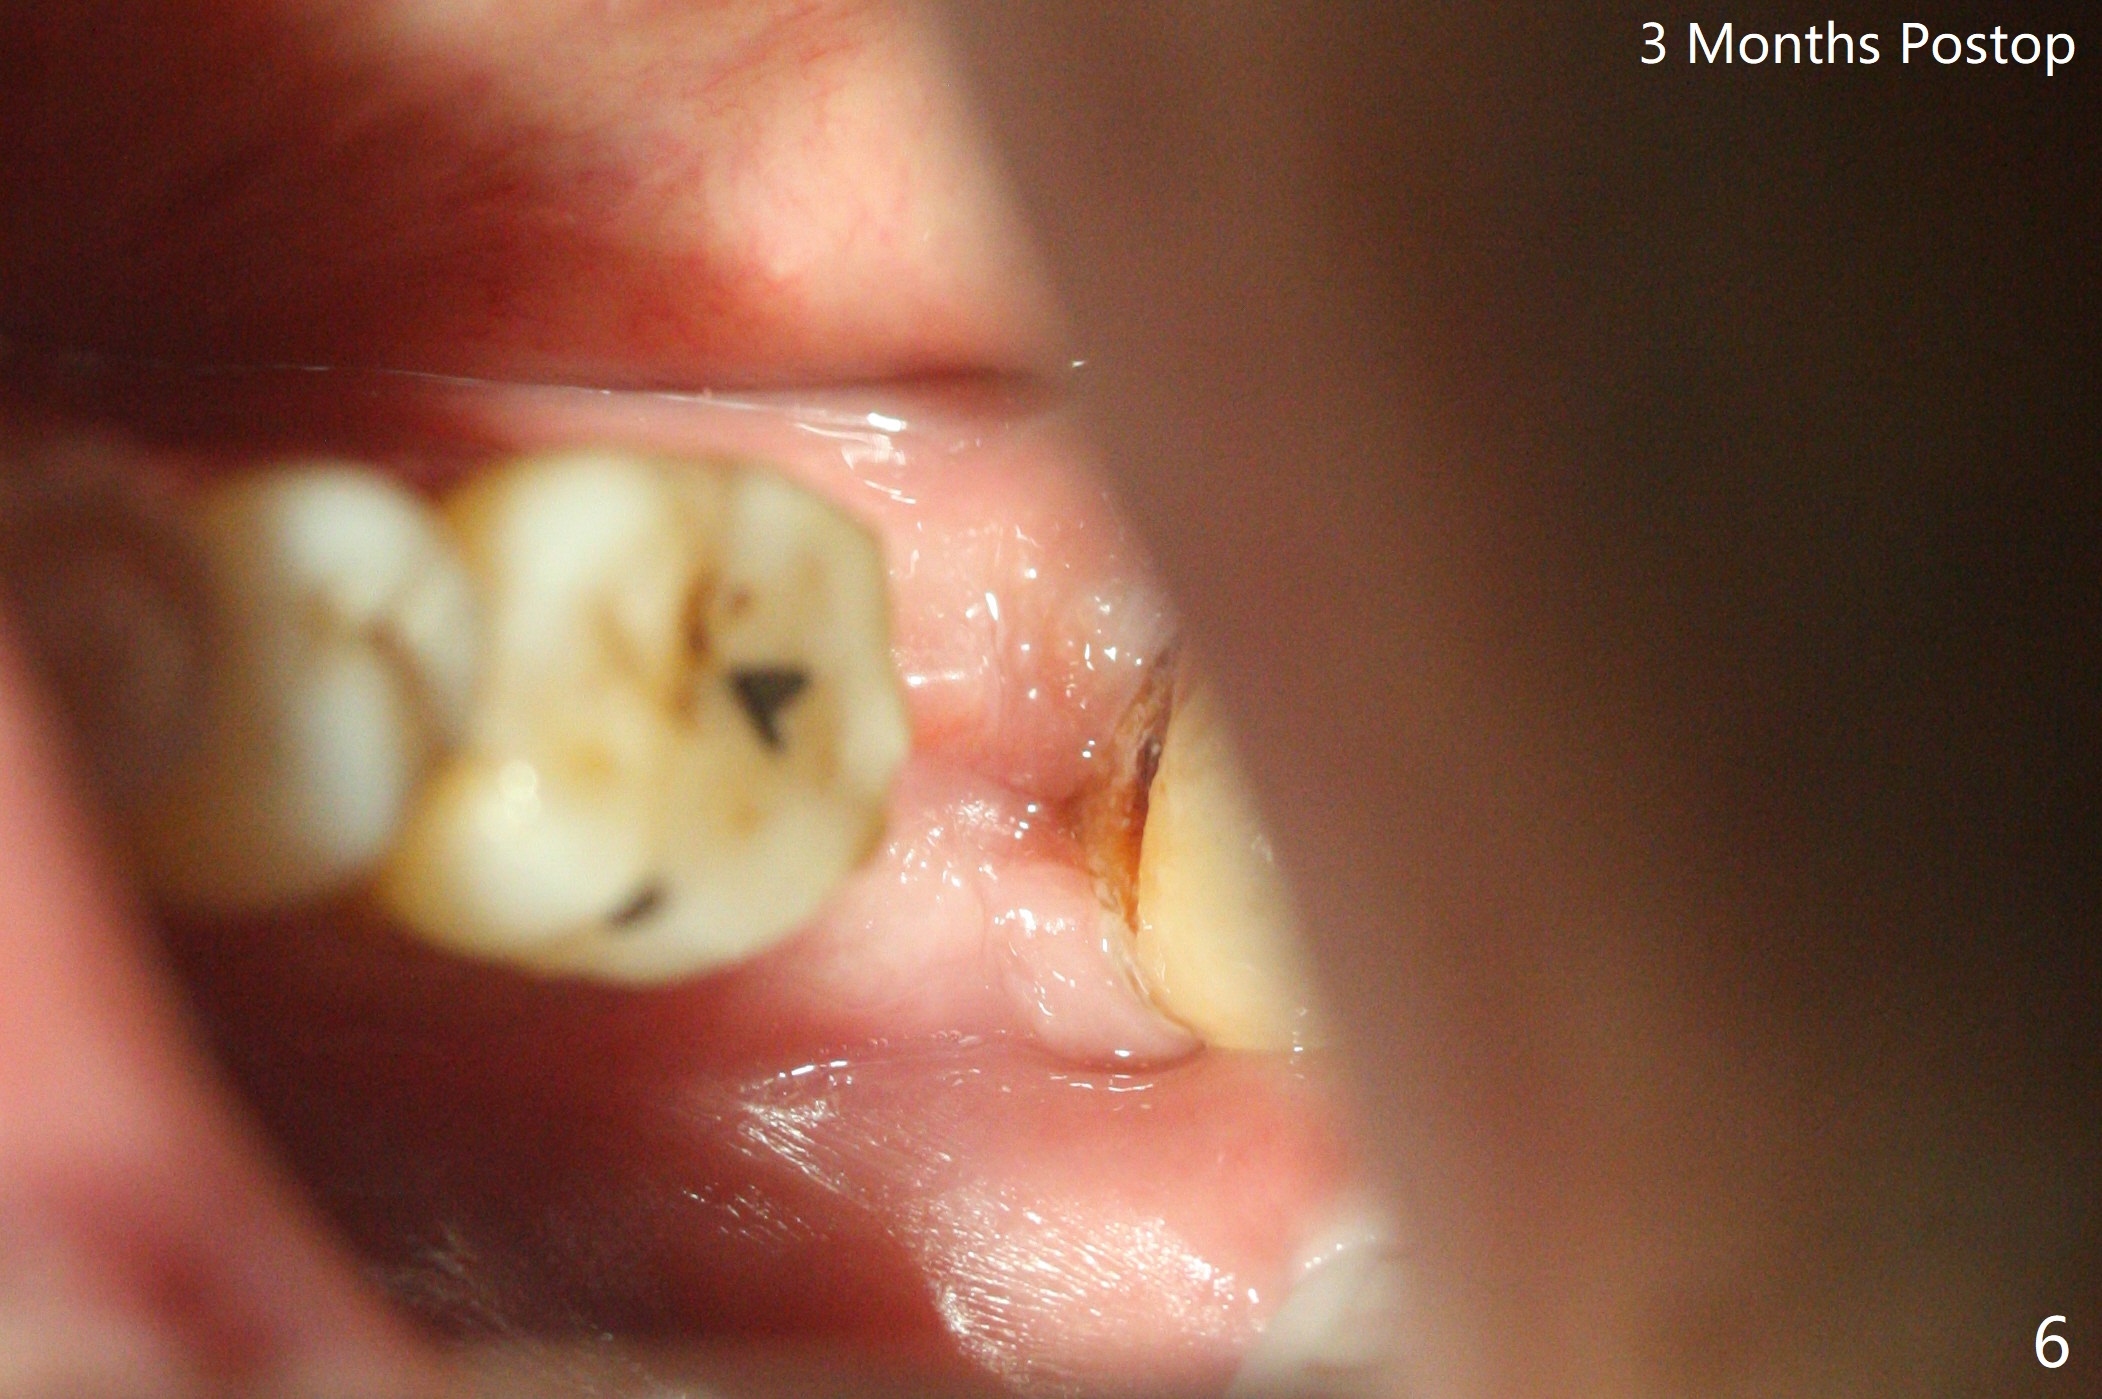

60岁男,吸烟,口腔卫生不好,不积极配合治疗,下前牙两个植体螺纹暴露,但是没有症状。两年中,左下七(图一,二)不能保留(图三),虽然六远中结石被清除(图三>),七位点保留(图四 *)时未能顺便在六远中填入骨粉(用血混合,胎盘膜覆盖)。四五个月后,七种植时将钻头骨粉放置于六远中缺损处,如何才能让骨粉在患处生根发芽?术后一个月,去除树脂敷料后,最表面骨粉未能被整合,下面骨粉好像已经与肉芽组织结合了(图五),其实根尖片应该拍摄证实这一点。吸烟者血供不好,愈合欠佳。术后三个月牙槽嵴宽(图六);高度稍微减低(图七)。术后4个月CT显示近中牙槽窝正好位于缺牙区正中(图八),所以植体必然进入近中窝(图九)。